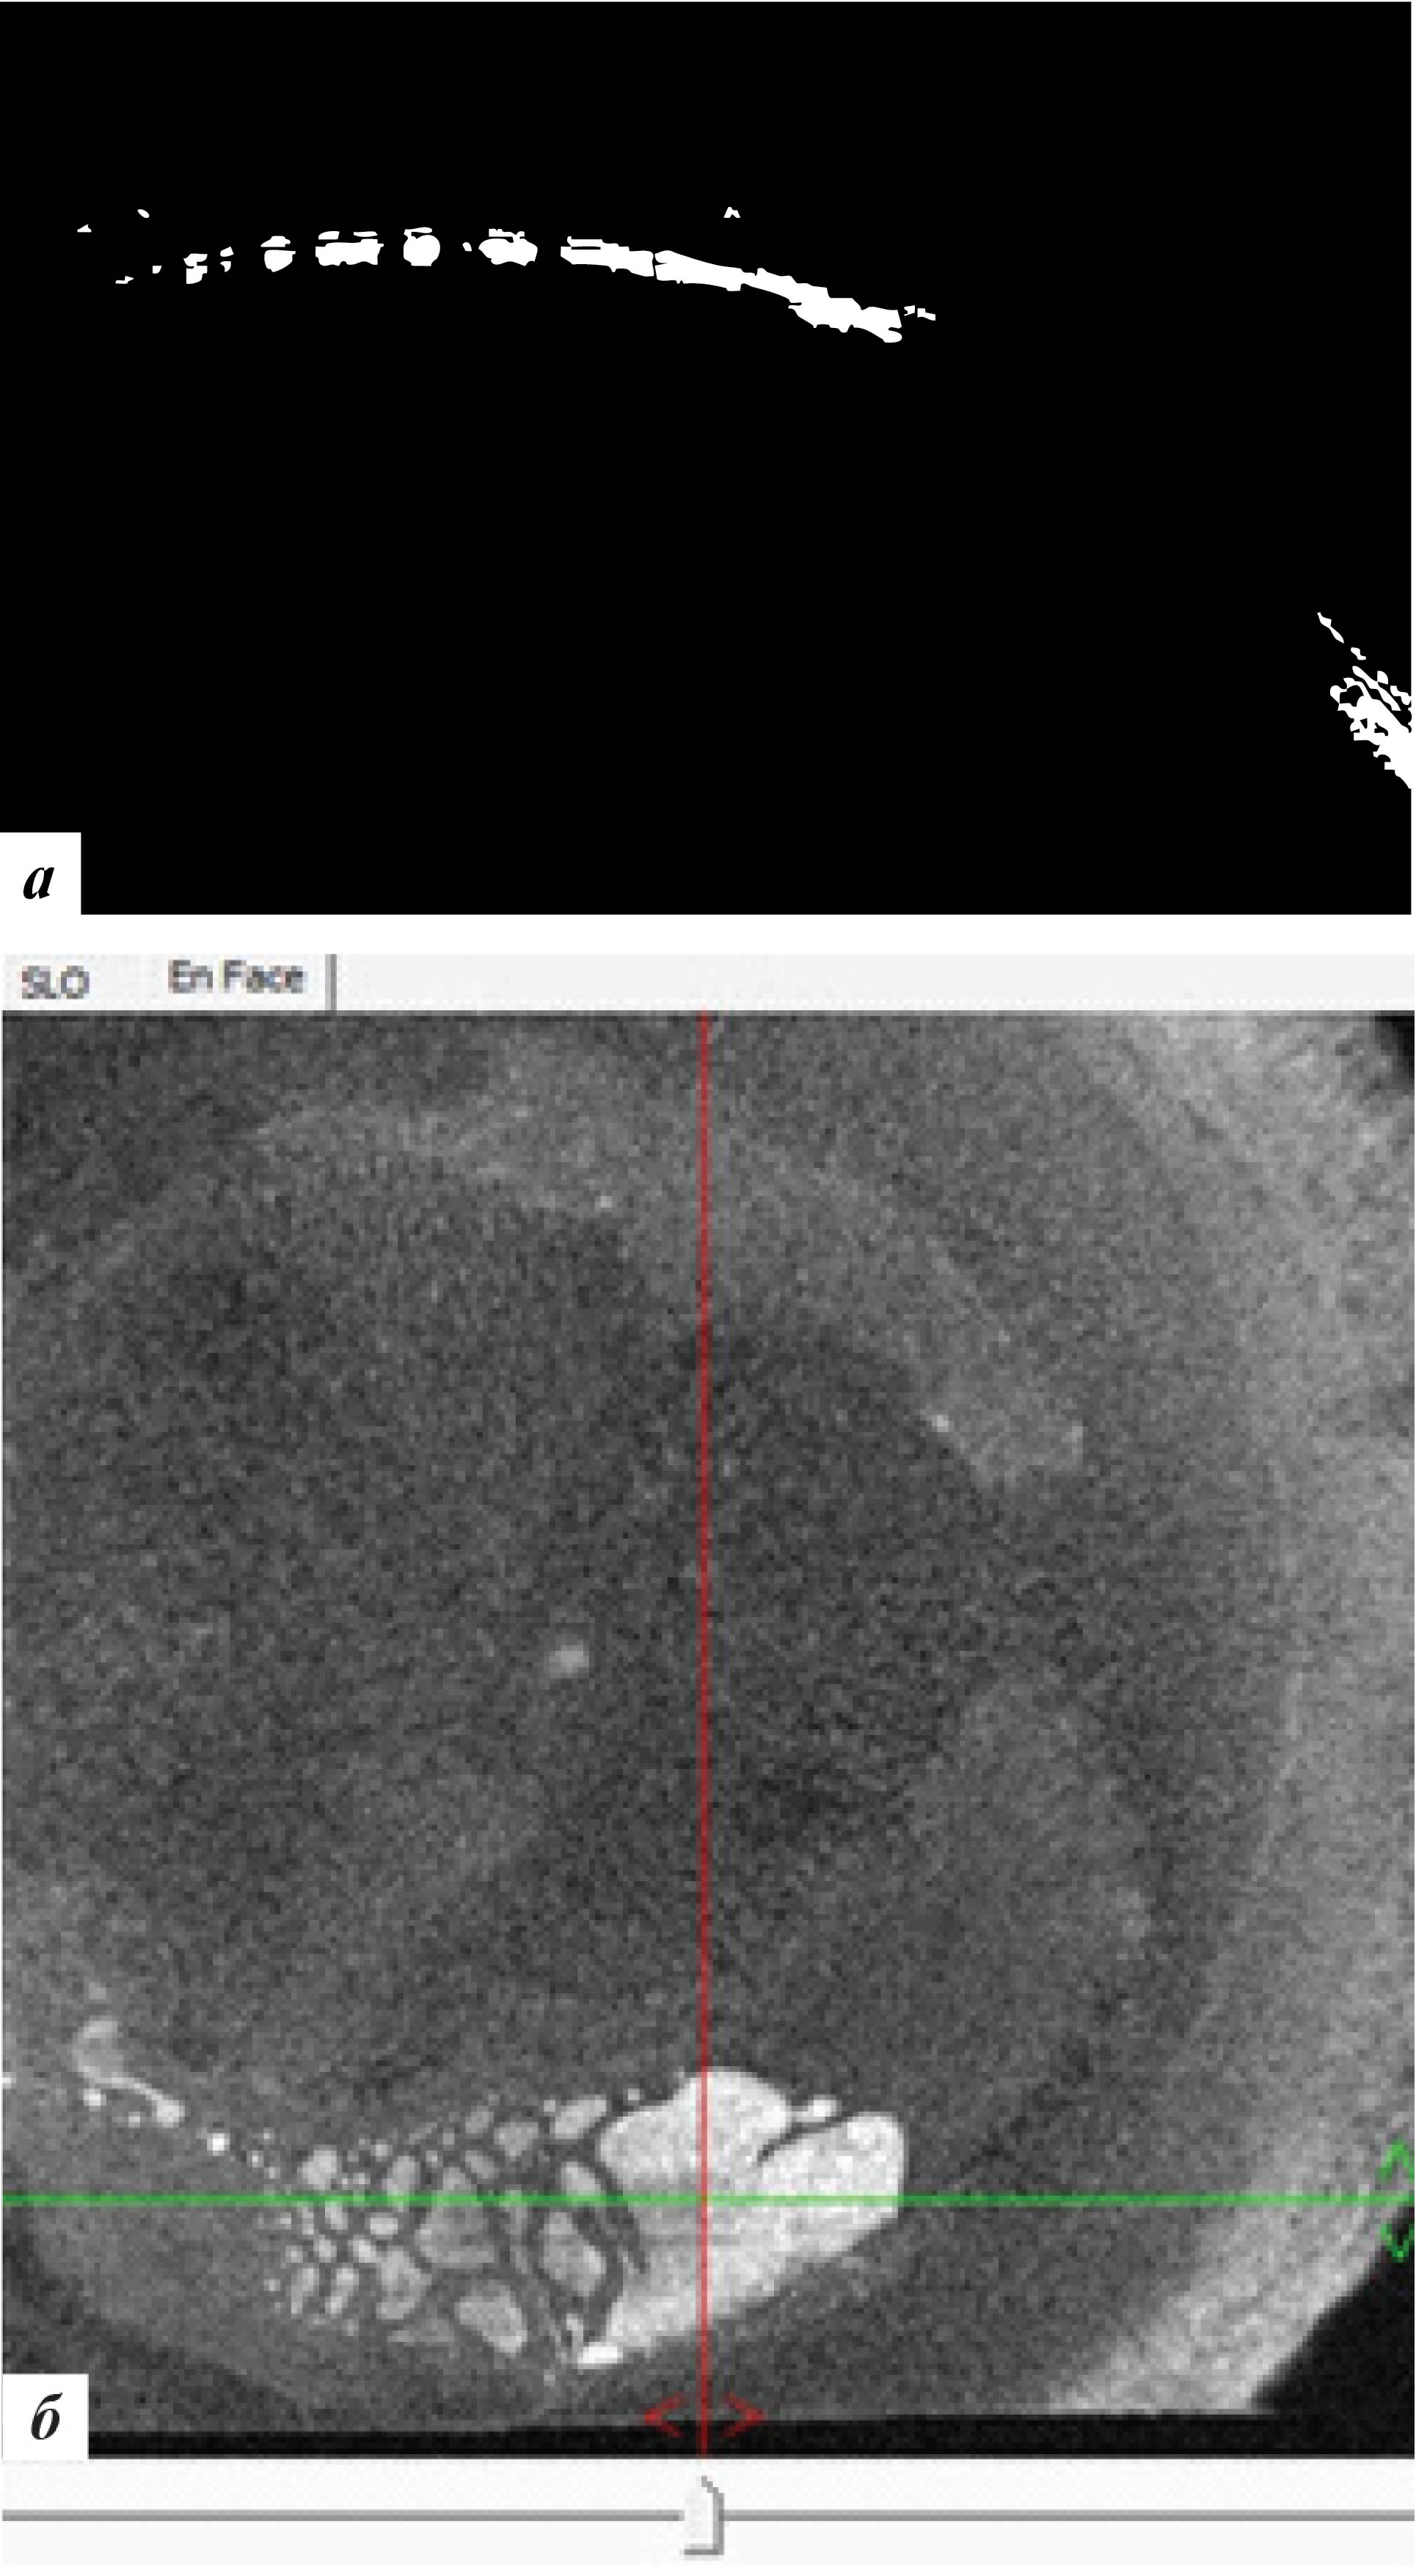

При офтальмобиомикроскопии глаз спокоен, в роговичном интерфейсе в центральной оптической зоне (ЦОЗ) и в параоптической зоне во внутреннем отделе определяется сливная зона вросшего эпителия 2 × 4 мм с зоной перифокального отека (рис. 3), что подтверждалось данными ОКТ роговицы (рис. 4). ПЭК OS: 2830 кл/мм2.

Рис. 3. Фото роговицы левого глаза до лечения

Рис. 4. Данные ОКТ роговицы левого глаза: а – горизонтальная проекция, б – фронтальная проекция